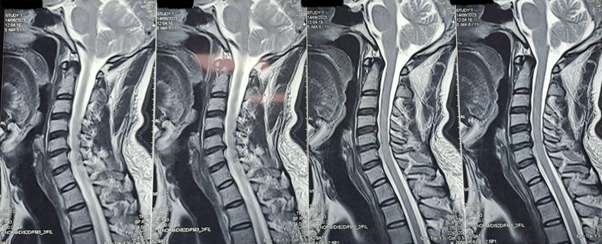

Workup imaging consisted of X-Ray and CT which demonstrated a fracture of the vertebral body of C5 and C6 and the spinous process of C7 (Figure 1). Due to clinical instability of the fractures and risk of neurological compromise, the patient was admitted to the department of neurosurgery. MRI was performed to clear any spinal cord lesion (Figure 2). A posterior cervical fixation guided under fluoroscopy was planned to stabilize the spinal column and prevent potential neurological injuries. Post operatively, analgesics and anti-inflammatory medications were prescribed and physical therapy was recommended to regain cervical function. Follow up demonstrated no neurological compromise, and the patient referred to minimal pain. Cervical rotation was conserved and flexion and extension was restricted (Figure 3).

Figure 2 MRI performed to rule out spinal cord lesion.